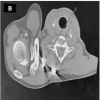

This is a 50-year-old healthy male who presented to our outpatient department (OPD) with chief complains of pain in the right shoulder region and recurrence of a deformity which was treated 3 weeks ago somewhere in another hospital. After taking a detailed history and going through the medical records available with him, it was found that he had Type-V ACJ injury post-fall from a bike in a road traffic accident (Fig. 1) for which he underwent surgical stabilization of the ACJ 3 days after the injury using a continuous FiberWire loop and double Endobutton construct. After 17–18 days of the surgery, the patient was lifting a heavy shutter with his left hand (normal) by bending forward. It was at this very moment he heard a popping sound and pain started in the right shoulder region. He visited our OPD and he was advised of plain radiographs of the right shoulder which reflected failed post-surgery ACJ dislocation (Fig. 2). The Endobutton passed through the coracoid base was lying superior to the base of the coracoid, which should be lying inferior to it indicating that the Endobutton had blown out of the coracoid drill hole. Non-contrast computed tomography was done to confirm the drill hole position in the coracoid base. A drill hole was not well visualized indicating the primary surgeon might have made an anterior, much superficial drill hole in the tip of the coracoid (Fig. 3).